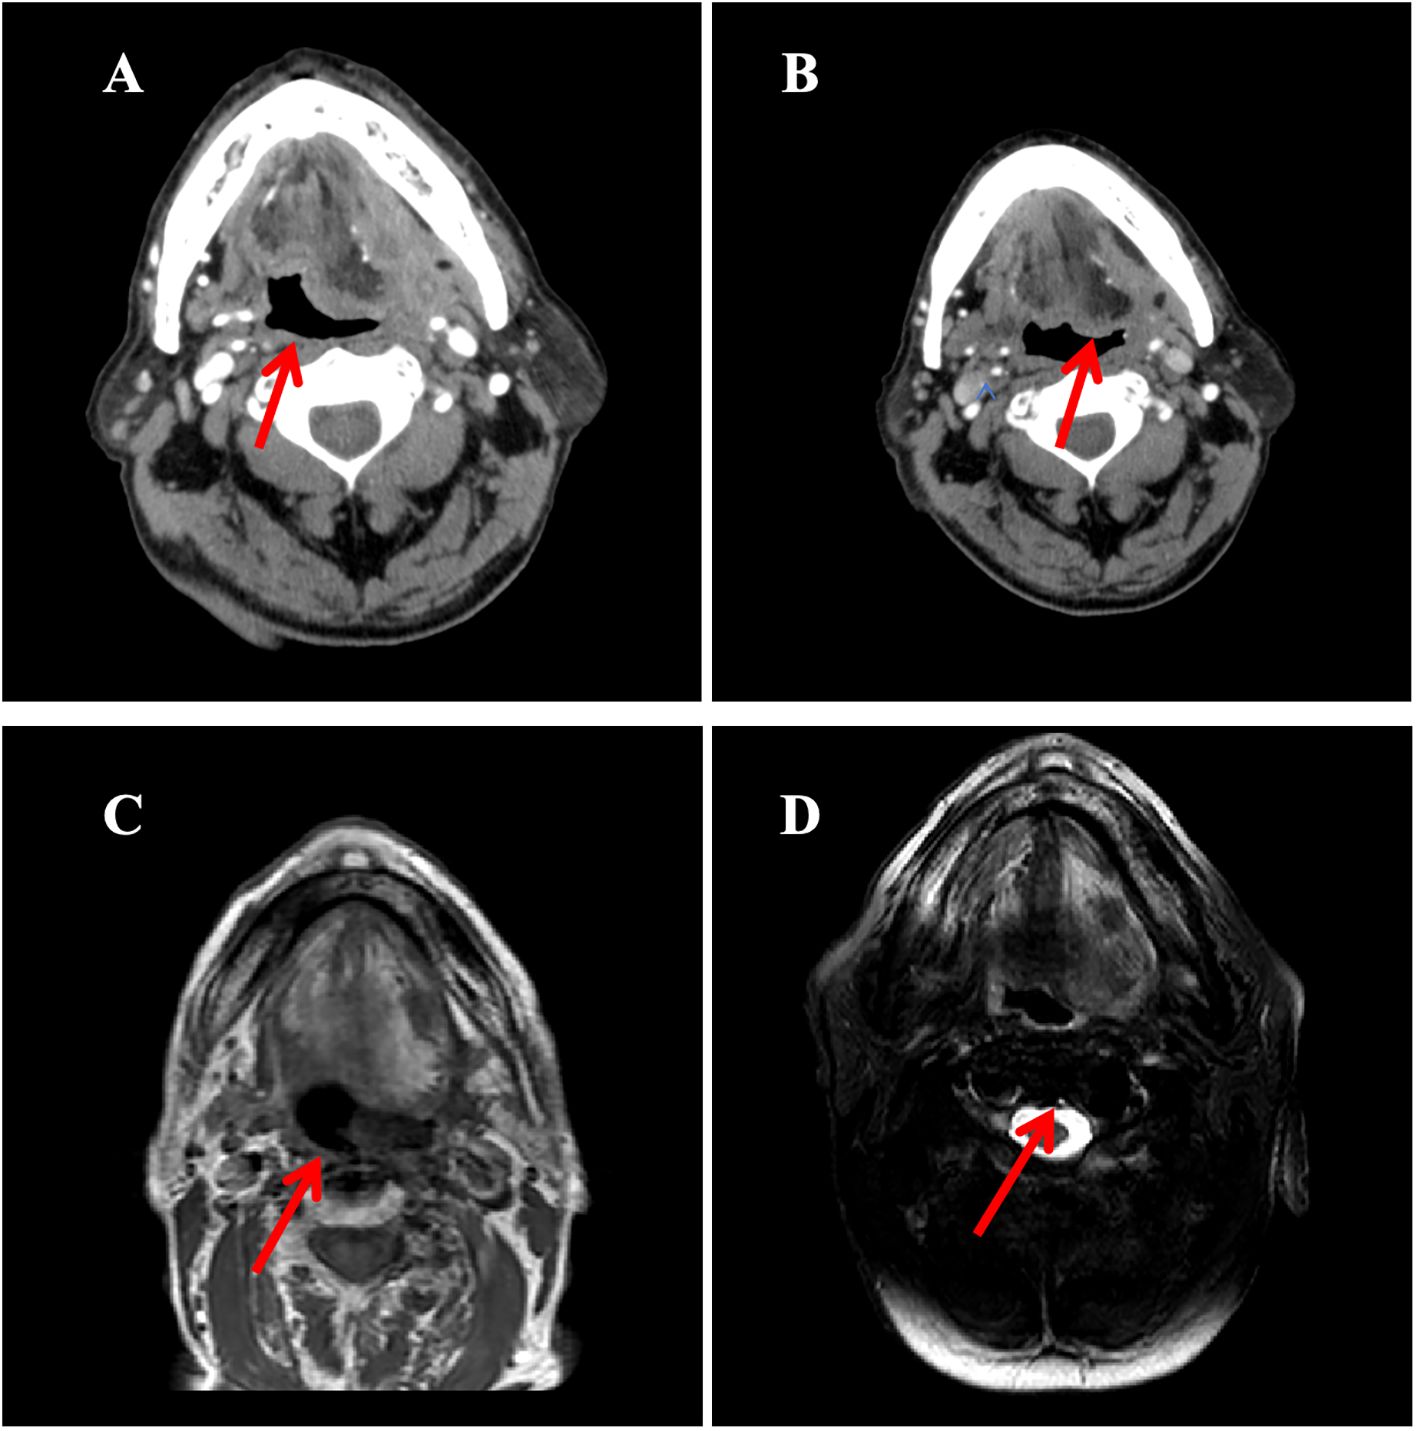

In October 2021, the patient experienced progressive worsening of symptoms and was subsequently transferred to our department for further management. Contrast-enhanced CT of the tongue demonstrated an irregular soft tissue density lesion (2.1×5.0 cm) in the left submandibular region with heterogeneous enhancement (Figure 3). Biopsy confirmed poorly differentiated invasive carcinoma with immunohistochemical profile consistent with the primary lesion (Table 1), confirming SDC origin.

Based on HER2 overexpression, advanced age, and poor performance status, the patient started trastuzumab (loading dose 8 mg/kg, maintenance dose 6 mg/kg q3w) combined with nab-paclitaxel (80 mg/m² on days 1 and 8, q3w) in November 2021. After four cycles, contrast-enhanced CT scan of the tongue showed a partial response (PR), with a reduction in the size of the submandibular lesion. Two additional cycles were administered as consolidation therapy, achieving radiological stability. Maintenance therapy with trastuzumab (6 mg/kg q3w) began in April 2022, with imaging follow-up scheduled every 12 weeks (every 4 treatment cycles). However, due to poor patient compliance, only four cycles were intermittently completed between April 2022 and June 2023.Imaging evaluations during this period confirmed stable disease (SD) according to RECIST 1.1 criteria (Figure 3).

Figure 3. The imaging evolution of a left submandibular mass in a patient during the treatment period from November 2021 to October 2023. (A) Contrast-enhanced neck CT (October 2021): Demonstrates an enhancing mass in the left submandibular region (maximum diameter: 5.0 cm); (B) Contrast-enhanced neck CT (February 2022, After 4 cycles of treatment): Shows significant reduction in the size of the mass compared to A (maximum diameter: 3.2 cm); (C) Contrast-enhanced MRI of the submandibular gland (axial T1-weighted image; March 2023): Reveals a mass in the sublingual region (maximum diameter: 1.7 cm); (D) MRI of the submandibular gland (axial T1-weighted image; June 2023): The mass measures 1.8 cm in maximum diameter, indicating size stability compared to C.

In October 2023, follow-up contrast-enhanced MRI of the head and neck revealed a lesion in the left sublingual region. Combined with clinical findings, this was assessed as disease progression according to RECIST 1.1 criteria. Targeted monotherapy was recommended but the patient did not adhere to the treatment regimen.

By March 2024, enhanced MRI of the mandible showed enlargement of the left sublingual mass (maximum diameter 4.1 cm) accompanied by progressive worsening of symptoms. Following comprehensive assessment, radiotherapy to the submandibular region was initiated on 9th April 2024 (total dose 60 Gy/30 fractions, 2 Gy/fraction), resulting in symptom relief. The patient remained in stable condition at the most recent follow-up in January 2025.